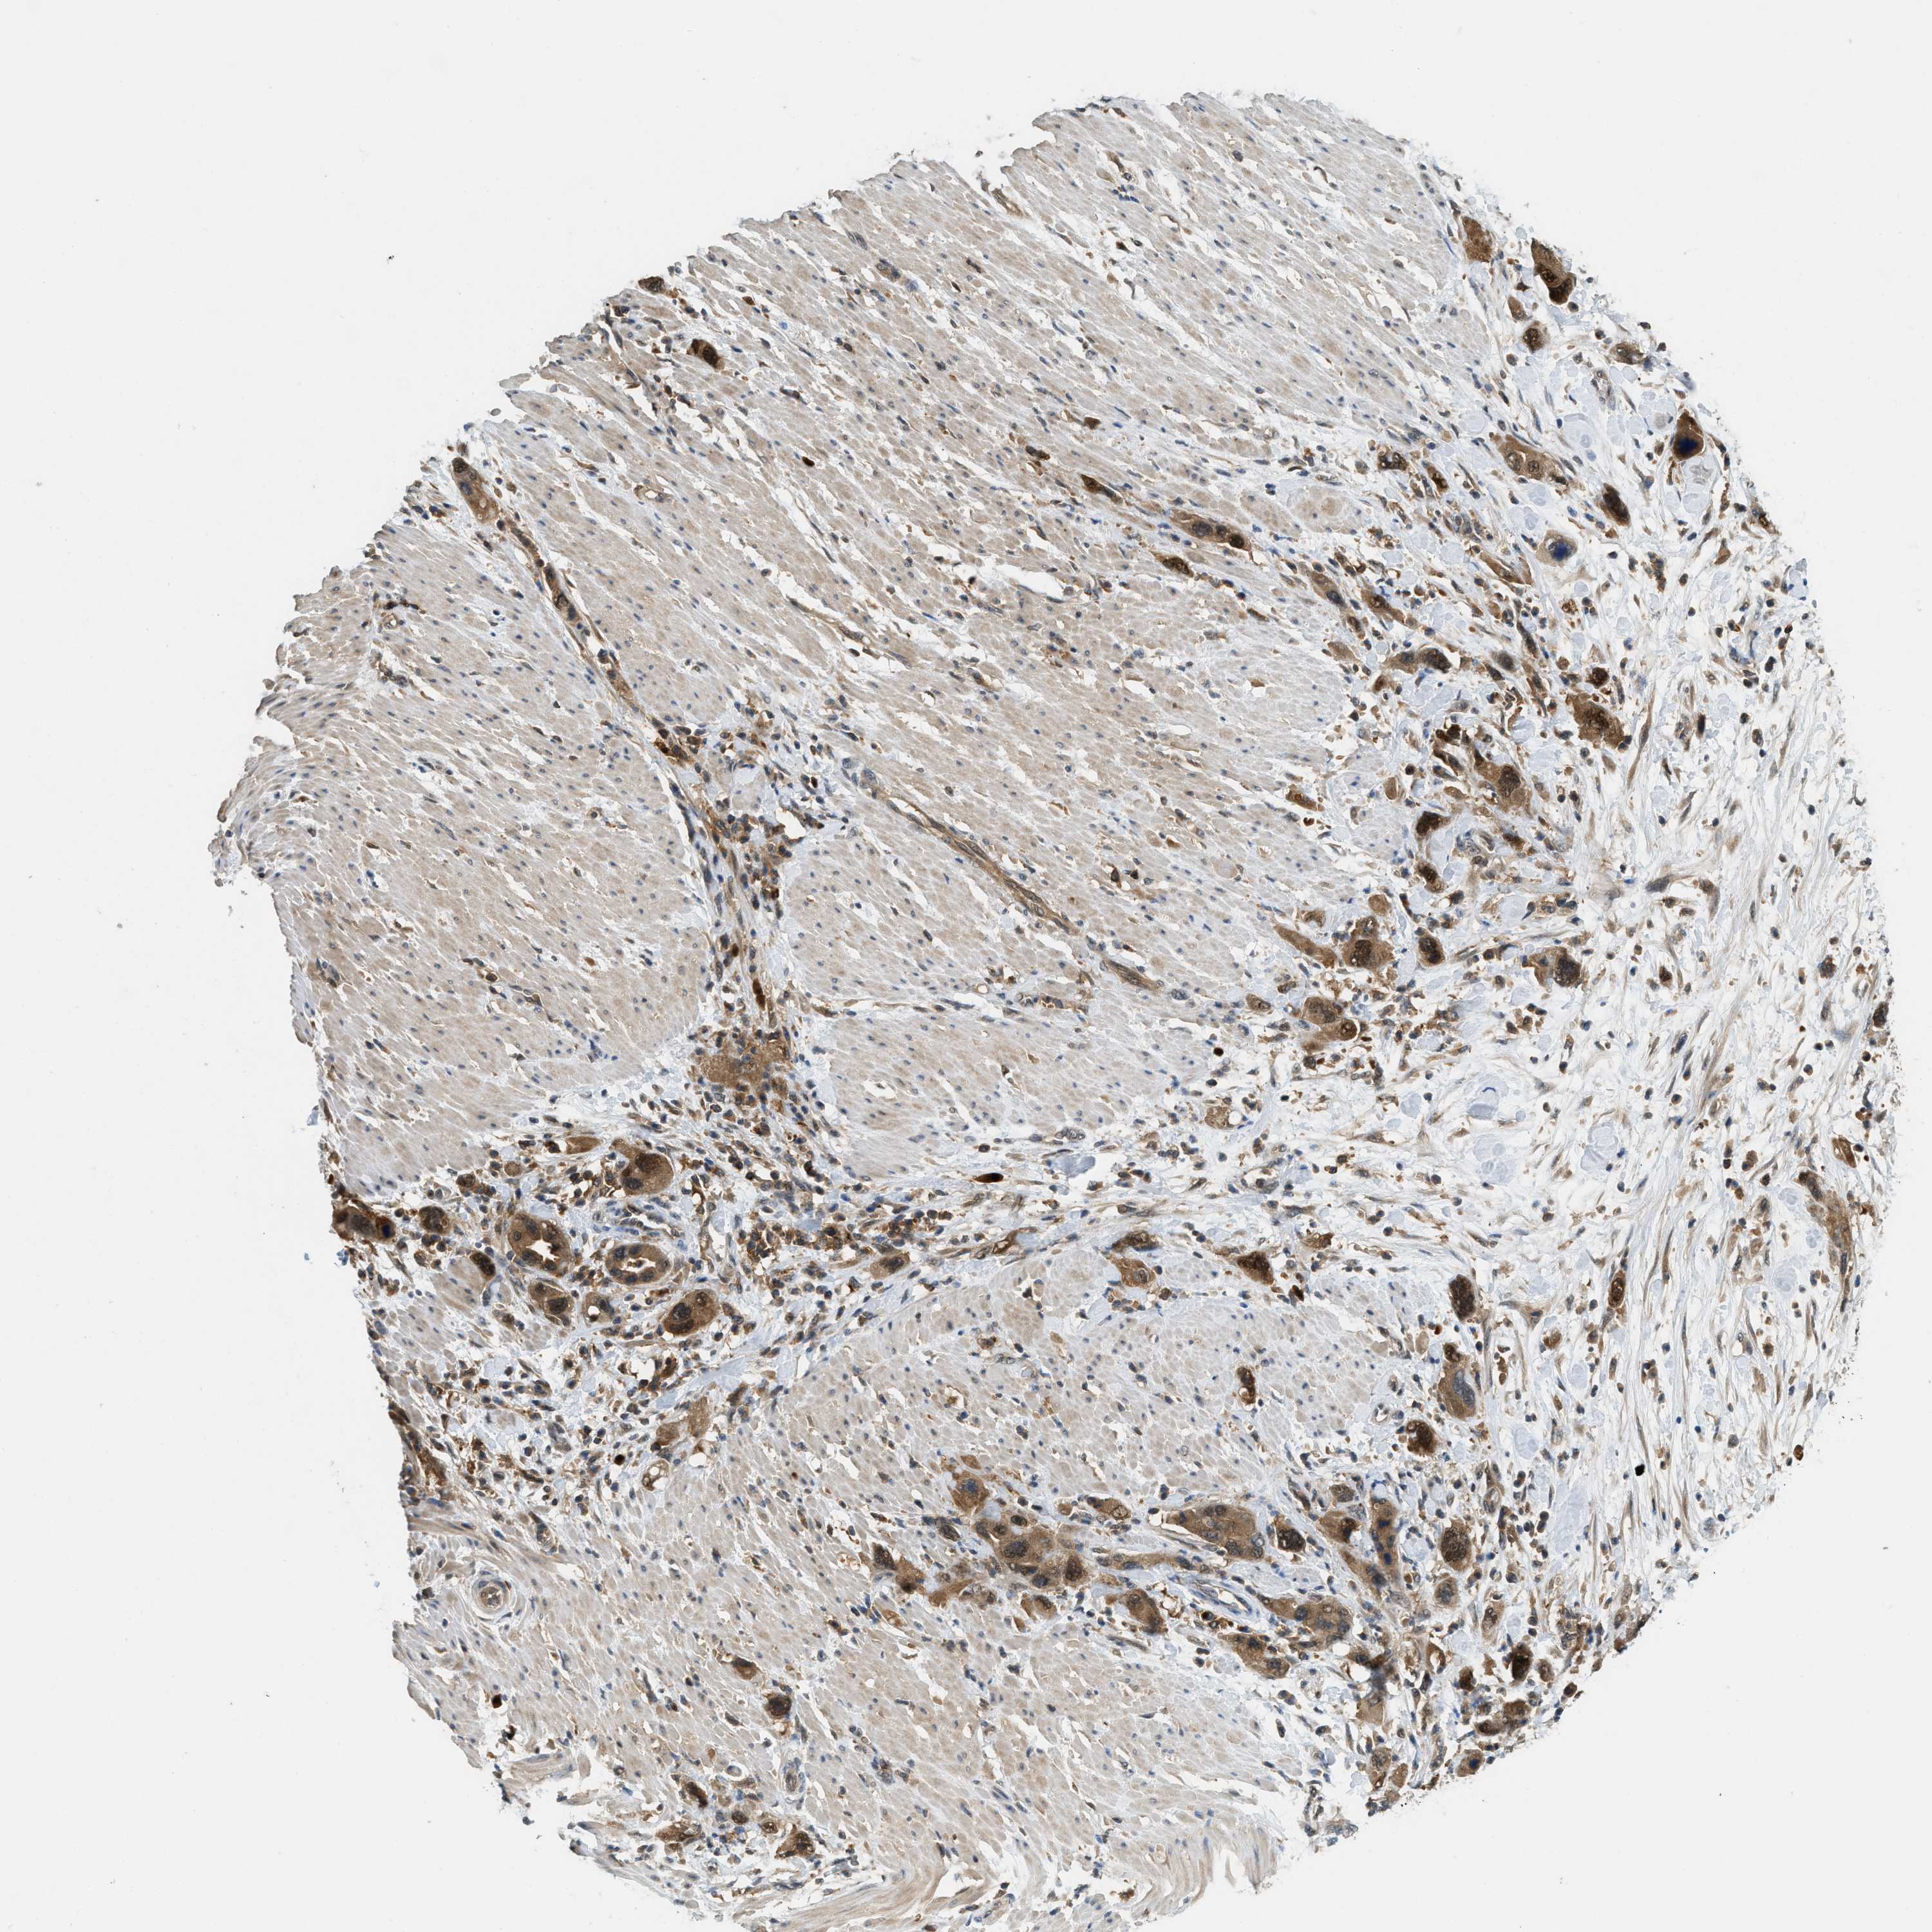

PANCREATIC CANCER - Protein expressioni

A mouse-over function shows sample information and annotation data. Click on an image to view it in a full screen mode. Samples can be filtered based on level of antibody staining by selecting one or several of the following categories: high, medium, low and not detected. The assay and annotation is described here.

Note that samples used for immunohistochemistry by the Human Protein Atlas do not correspond to samples in the TCGA dataset.

Antibody stainingi

Antibody staining in the annotated cell types in the current human tissue is reported as not detected, low, medium, or high, based on conventional immunohistochemistry profiling in selected tissues. This score is based on the combination of the staining intensity and fraction of stained cells.

Each image is clickable and will lead to virtual microscopy that enables deeper exploration of all samples and also displays staining intensity scores, fraction scores and subcellular localization as well as patient and tissue information for each sample.

Antibody HPA014657

Staining

High

Medium

Low

Not detected

Intensity

Strong

Moderate

Weak

Negative

Quantity

>75%

75%-25%

<25%

None

Location

Nuclear

Cytoplasmic/membranous

Cytoplasmic/membranous,nuclear

Adenocarcinoma, NOS